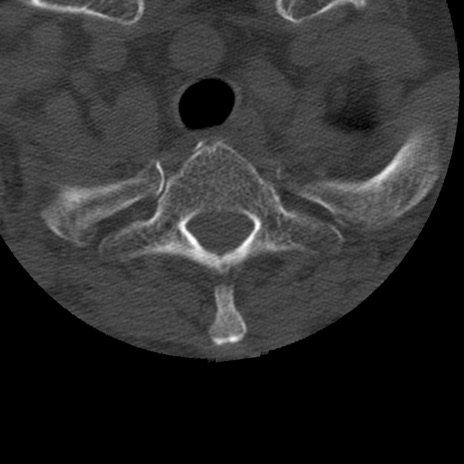

症例50 頚椎CT(横断像)

冠状断像